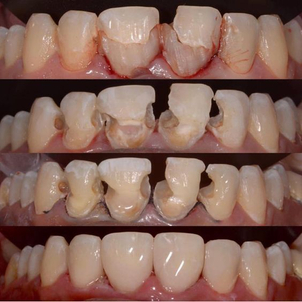

Antes y Después Clínica Dental Exceldent Plus